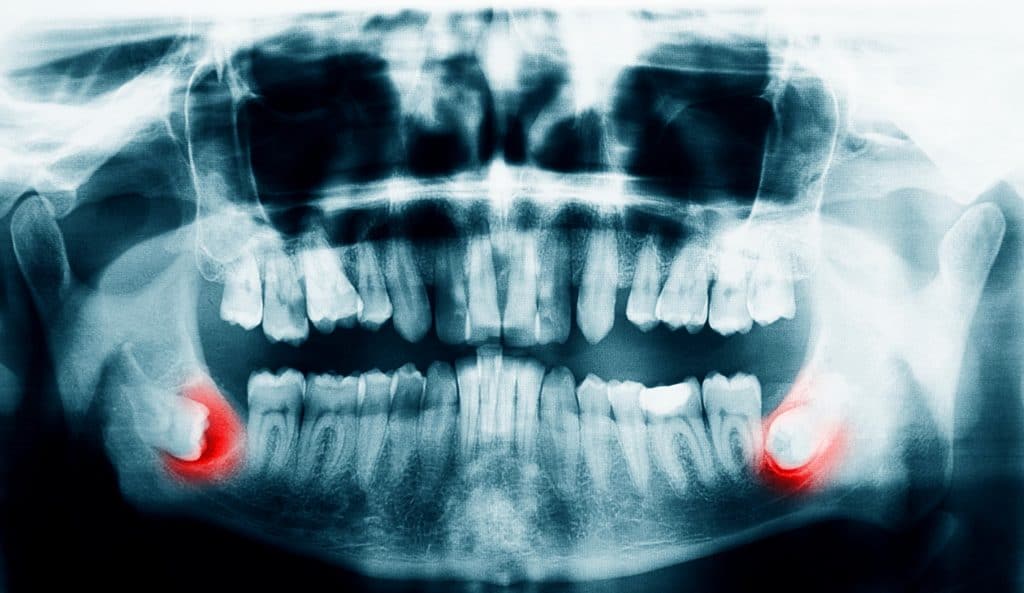

Au maxillaire inférieur, la dent est souvent couchée à l’horizontale et vient buter contre la seconde molaire. Cette position bouscule toutes les dents inférieures et peut créer une zone profonde impossible a nettoyer derrière la seconde molaire, et ainsi permettre le développement d’ une carie de la racine de la dent adjacente, entrainant la nécessité de l’extraction des deux dents.

L’évolution de l’Homme moderne crée une diminution du volume de la partie inférieure du visage et une réduction de l’os de la mandibule, ces dents se retrouvent de plus en plus souvent dans des situations anormales, entrainant des pathologies qui nécessitent leurs extractions. Mais le plus souvent les patients n’ont pas conscience de l’éruption de leurs dents de sagesse et du bon placement sur les arcades dentaires, tout s’est donc bien passé, silencieusement.